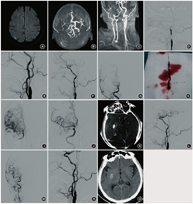

患者男,72岁。因"突发言语不清伴左侧肢体活动不灵4 h"于2019年12月入院。既往高血压病史9年,收缩压最高为190 mmHg(1 mmHg=0.133 kPa),未规律口服降压药,血压控制差;鼻咽癌病史20余年,多次行放射治疗。入院查体:血压120/60 mmHg,美国国立研究院卒中量表评分(NIHSS)12分,格拉斯哥昏迷评分(GCS)13分,改良Rankin量表评分(mRS)4分。意识清楚,精神差,语言含糊不清,回答欠合作;双眼向右侧凝视,双侧瞳孔等大、等圆(直径约3 mm),对光反射迟钝;鼻唇沟对称,口角相等,伸舌居中;双侧肢体肌张力正常,左侧肢体肌力0级,右侧肢体肌力Ⅴ级;左侧巴宾斯基征(+),右侧(-)。急诊头颅CT提示"未见明显异常",考虑急性脑梗死,给予阿替普酶(63 mg)静脉溶栓,症状未见明显好转,急诊行头颅MRI+MR血管成像(MRA)提示:右侧基底核、额顶叶散在急性梗死,右侧颈内动脉及MCA栓塞(图1A~C)。当日在气管插管全身麻醉下行脑血管造影+右侧颈内动脉球囊扩张+右侧MCA取栓+右侧颈内动脉支架置入术,术中造影见右颈内动脉起始段闭塞(图1D),更换8F导引导管(美国强生公司)置于右侧颈总动脉远端,泥鳅导丝缓慢通过闭塞段,撤出导丝后造影见对比剂缓慢显影至右侧颈内动脉末端,大脑前动脉显影,MCA闭塞不显影(图1 E)。依次用MINI TREK球囊(美国Abbott公司)、Viatrac 14 Plus球囊(美国Abbott公司)扩张右侧颈内动脉近段(图1 F)。将5F Navien导管(美国eV3公司)置于颈内动脉床突段,Rebar-18微导管(美国eV3公司)在Avigo微导丝(美国eV3公司)的引导下置于右MCA上干,手推对比剂显示MCA上干显影,Solitaire FR支架(美国eV3公司)取栓并抽吸Navien导管,见有少量栓子取出,复查造影见右MCA不显影(图1G),相同方法再次取栓抽吸见有暗红色栓子取出(图1H),复查造影显示右侧MCA及各分支显影良好,右MCA血流达血流灌注(TICI)分级3级(图1I,J),Dyna CT显示右侧基底核区对比剂外渗(图1K)。开通血管约1 h后再次复查右颈总动脉造影,见右颈内动脉近段血流明显减慢,考虑血流不能维持(图1L,M)。于Navien导管内缓慢推入0.25 mg替罗非班,外周静脉以0.25 mg/h泵入替罗非班,在Spider FX保护伞(美国Ev3公司)的保护下顺利置入RX Acculink(美国eV3公司)支架并释放,造影见右颈内动脉起始段狭窄明显改善,远端大脑前动脉、MCA及各分支显影良好(图1N)。术后给予替罗非班(0.25 mg/h)持续泵入24 h,术后第2天复查头颅CT未见明显出血(图1O),给予阿司匹林100 mg(1次/d)+氯吡格雷75 mg(1次/d),调控血压维持在低于平时血压20 mmHg,并给予甘露醇、依达拉奉等药物防治脑缺血再灌注损伤,患者症状好转,NIHSS为3分。术后第9天NIHSS为0分,mRS为0分,神经系统查体未见明显阳性体征。